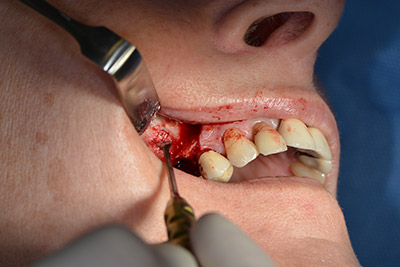

An absorbable membrane was used as the barrier in the buccal direction and covered the augmentation. Finally, saliva-proof sutures were placed (Fig. 15 to 19).

Augmentation with autologous bone

Image 15

Image 16

Implantation

Image 17

Implantology

Image 18

saliva-proof wound closure

Image 19